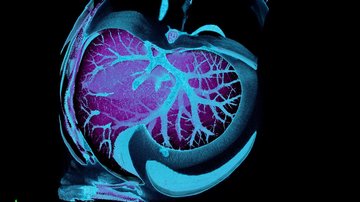

Vrbacký M, Kovalčíková J, Chawengsaksophak K, Beck IM, Mráček T, Nůsková H, Sedmera D, Papoušek F, Kolář F, Sobol M, Hozák P, Sedlacek R, Houštěk J. Knockout of Tmem70 alters biogenesis of ATP synthase and leads to embryonal lethality in mice. Hum Mol Genet. 2016 Aug 31. pii: ddw295. [Epub ahead of print]